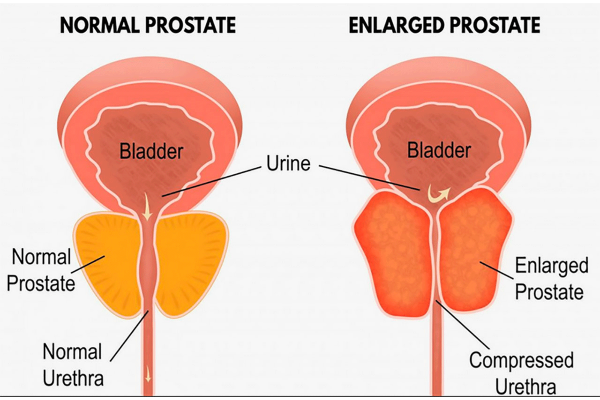

BPH is a non-cancerous condition in which the prostate gland becomes enlarged. The prostate is a small gland located just below the bladder in men. As the prostate enlarges, it can press against the urethra (the tube that carries urine out of the body). This can cause urinary symptoms such as difficulty starting to urinate, a weak urine stream and the need to urinate frequently, especially at night.

Symptoms of BPH and Other Issues

As stated previously, BPH is a condition that causes the prostate gland to become excessively enlarged. While this may seem trivial at face value, it’s a condition that can lead to many problems. The prostate is a small gland located below the bladder in men and as it enlarges, it can press against the urethra (the tube that carries urine out of the body) and cause urinary symptoms.

- Difficulty starting to urinate: As the prostate enlarges, it can put pressure on the urethra and make it difficult to start urinating.

- Weak Urine Stream: As the prostate enlarges, it can also put pressure on the urethra and make it challenging to maintain a strong urine stream.

- Frequent Urination: As the prostate enlarges, it can also pressure the bladder.

How the Prostate Works

The prostate gland is an organ located near the urethra in the male reproductive system. Its primary role is to produce and secrete a milky fluid known as prostate fluid. This fluid helps sexual health. The prostate also regulates urinary function, controlling urine flow from the bladder.

The prostate is under the control of testosterone and DHT. These hormones are responsible for the prostate gland’s development and maintenance. As men age, testosterone levels decrease, but DHT levels remain the same. This can cause prostate cells to grow and divide, leading to an enlarged prostate (BPH)

The prostate works by controlling the flow of urine from the bladder. When the bladder contracts, the prostate responds, allowing urine to be slowly released through the urethra. The prostate also helps to control sexual health.